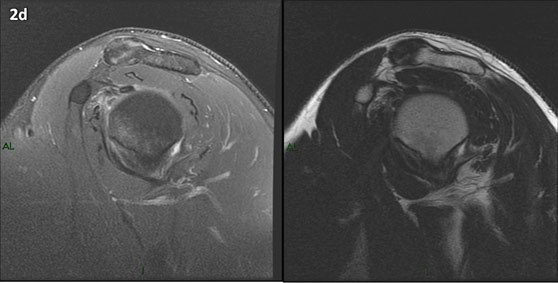

Figura 2 (a-j): Imagens consecutivas de RM no plano sagital nas ponderações T2 com supressão de gordura (DP SG) à esquerda e T2 à direita. Clique na seta para passar as imagens.

Figura 2 (a-j)': Imagens consecutivas de RM no plano sagital nas ponderaçõesT2 com supressão de gordura (DP SG) à esquerda e T2 à direita. Clique na seta para passar as imagens.

Figura 2a’ mostrando os tendões do subescapular (seta rosa), da cabeça longa do bíceps (seta verde), do supraespinhal (seta vermelha), do infraespinhal (seta laranja) e do redondo menor (seta amarela).

Figuras 2b a 2j’: Acompanhando o tendão do redondo menor (seta amarela fina) é possível notar lipossubstituição ao redor da junção miotendínea (setas amarelas grossas) e a atrofia principalmente da porção mais lateral (seta salmão). A porção mais medial (seta branca) tem volume preservado.

Repare que estas alterações também não são evidentes nas imagens com supressão de gordura no plano sagital.